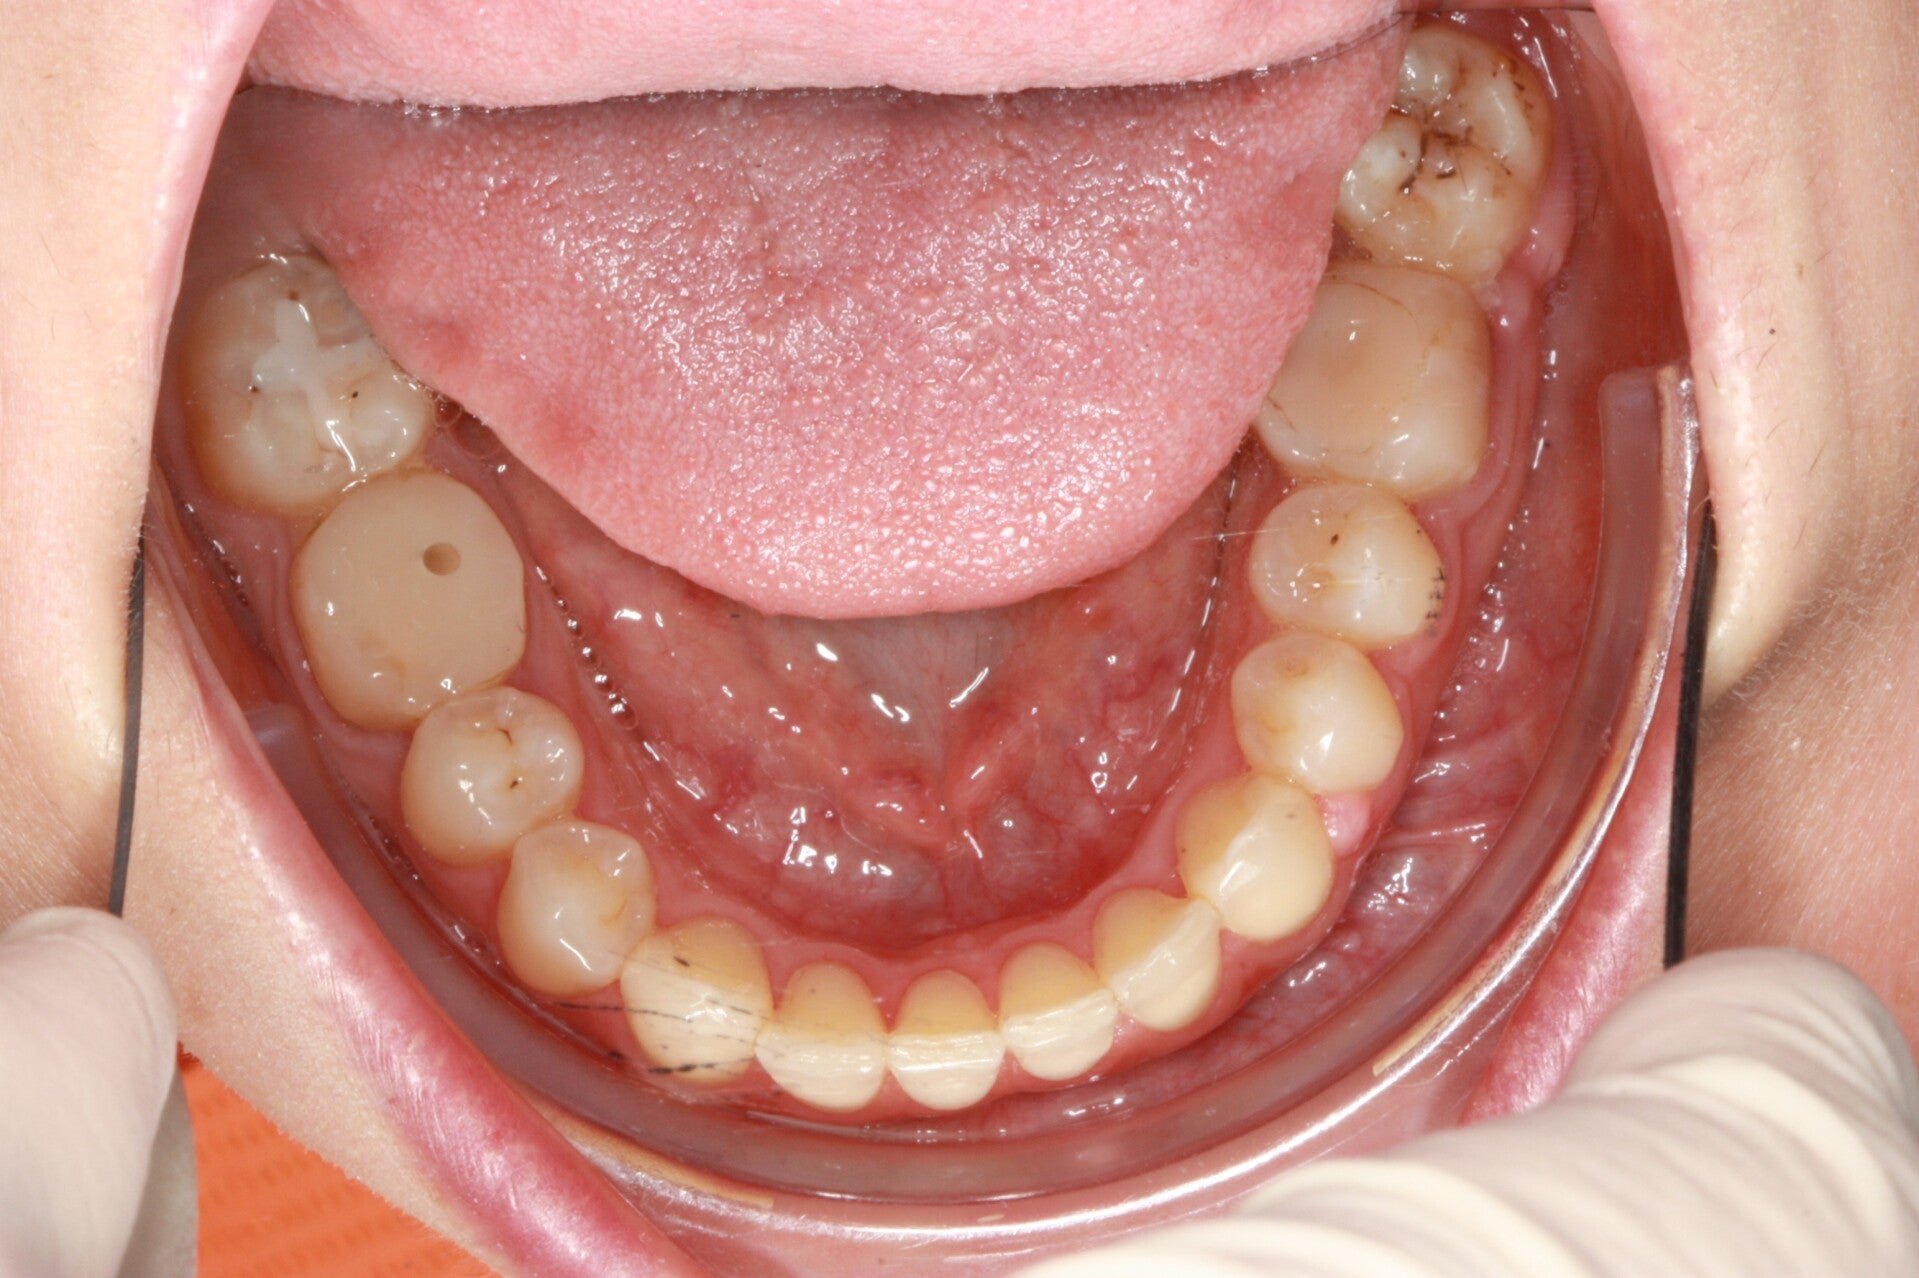

FOTO FINALI DOPO 24 MESI CIRCA DI TERAPA ORTODONTICA FISSA

Abbiamo appena portato a termine questo caso che presentava in arcata superiore il primo premolare di sinistra completamente fuori arcata sovrapposto al secondo premolare ed il canino ruotato.

in arcata inferiore invece abbiamo estratto il secondo molare di sinistra perso per carie deostruente e mesializzato il terzo molare in modo da chiudere lo spazio e non ricorrere all'inserimento di protesi implantare.